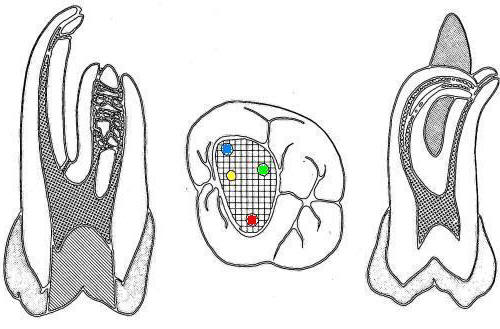

1º Molar Superior

La flecha amarilla indica un posible cuarto conducto. Debe abrir hacia mesial  para eliminar la pared marcada en un circulo celeste, a la misma profundidad que el conducto mesio-vestibular.  Ver imagen derecha.

Entradas de los conductos que más frecuentemente se hallan en los primeros molares superiores(1,2,23,27):

El poder de magnificación del MO con visión indirecta y luz coaxial permite localizar las entradas de los conductos calcificados. Incluso los más pequeños y difíciles de ver como el conducto mesio-palatino (Ver flecha amarilla imagen superior izquierda)